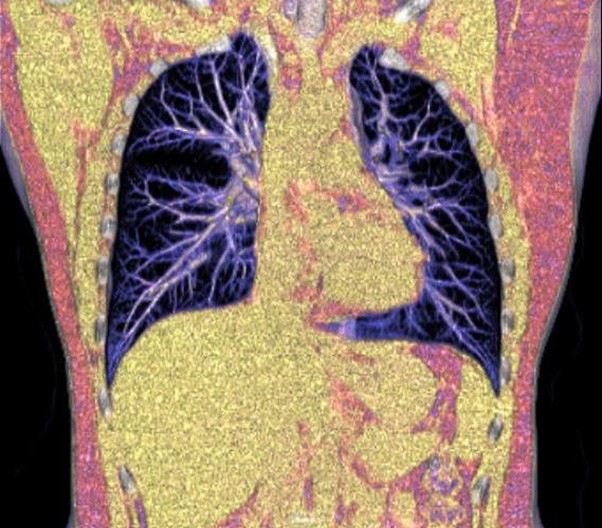

The 1024-pixel image matrix brings superior image clarity (0.6 mm slice thickness) and stimulates the early detection of small lesions, thus improving diagnostic reliance.

NDI NanoDose Iteration Algorithm (NDI) is an innovative iterative technique for image reconstruction that takes full advantage of deep learning in anatomical structure in image space as well as model-driven iteration involving tube and detector in projection space, with the aim to generate sharp and high-resolution images at the lowest possible dose.